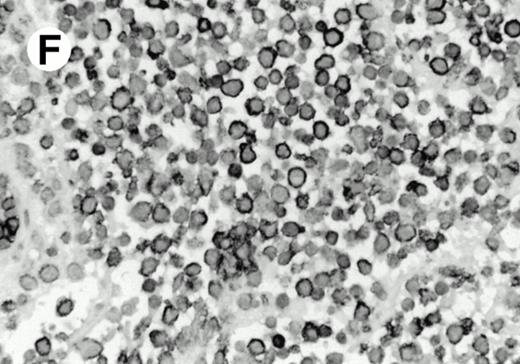

Both paraffin-embedded tissues and frozen sections (with or without heat antigen retrieval) were prepared for immunohistology as described in Materials and Methods. KPL1 stained numerous T cells in the T-zone (TZ) of a human tonsil (Fig 8A), but did not stain B cells in the mantle zone (M) or germinal center (GC) of the secondary follicles. Macrophages in the germinal center stained but follicular dendritic cells did not (Fig 8A). Just outside the germinal center, intense KPL1 staining of overlying plasma cells was observed. A high-power magnification (Fig 8B) shows this intense staining of plasma cells which surround the germinal centers. Subepithelial plasma cells also stained with KPL1 (data not shown), as did plasma cells around vessels in the skin (Fig 8C); these plasma cells costained with the plasma cell marker VS38 (Fig 8D). Thus, B cells located in germinal centers either lack the KPL1 epitope, or express it at levels which are not detected by these methods, whereas plasma cells in numerous sites express high levels. Similarly, four IL-6–dependent human myeloma cell lines expressed high levels of the KPL1 epitope (Diane Jelinek, personal communication, March 1997). Both cortical and medullary lymphocytes in the thymus stained with KPL1 (data not shown). Langerhans cells, bone marrow–derived antigen presenting cells which reside in the suprabasilar region of the epidermis, were also positive for KPL1 (Fig 8E). Langerhans cells in the tonsillar epithelium also stained with KPL1 (data not shown). Langerhans cells in soft tissue also stain with both KPL1 (Fig 8F) and CD1a (Fig 8G).

(E) Paraffin section of skin stained with KPL1. The Langerhans cells in epidermis and superficial dermis stain intensely in this example of Langerhans cell histiocytosis. The stained dendritic processes are apparent in the epidermis. (F) Langerhans cells in soft tissues also stain with KPL1. (G) Identification of Langerhans cells in (F) is confirmed by costaining with CD1a (immunoperoxidase with hematoxylin counterstain).